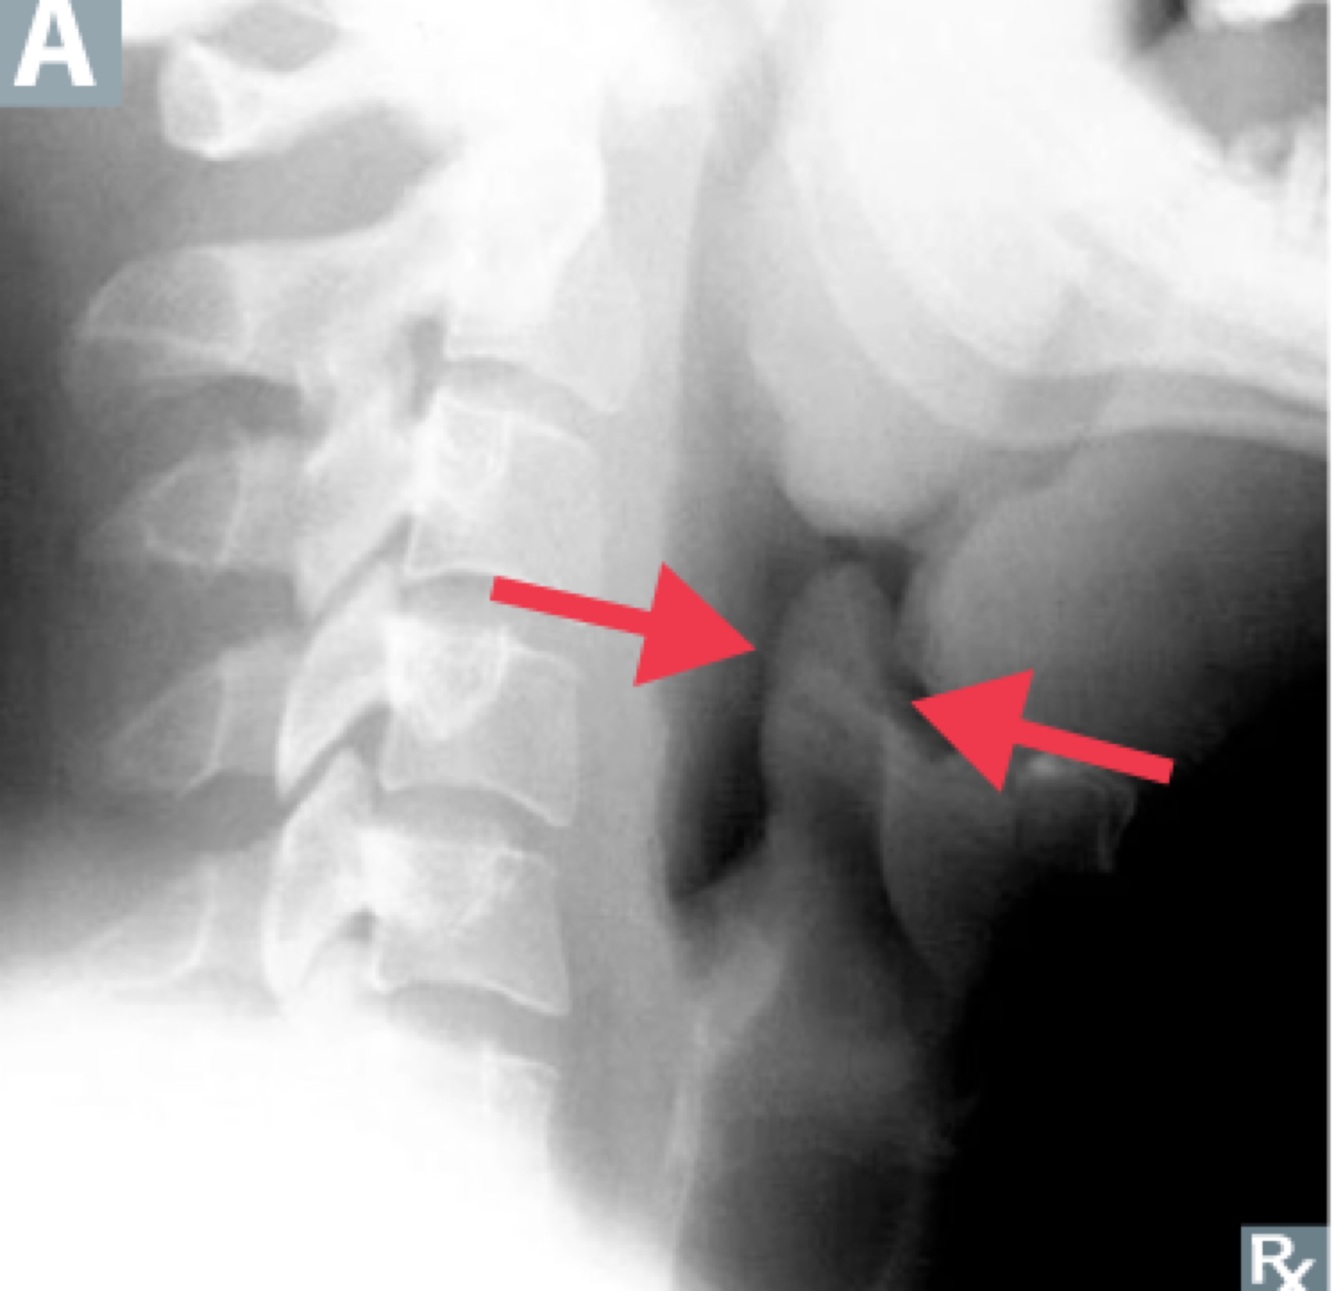

H.influnza : acute epiglottis (“thumb sign” on lateral neck x-ray”)